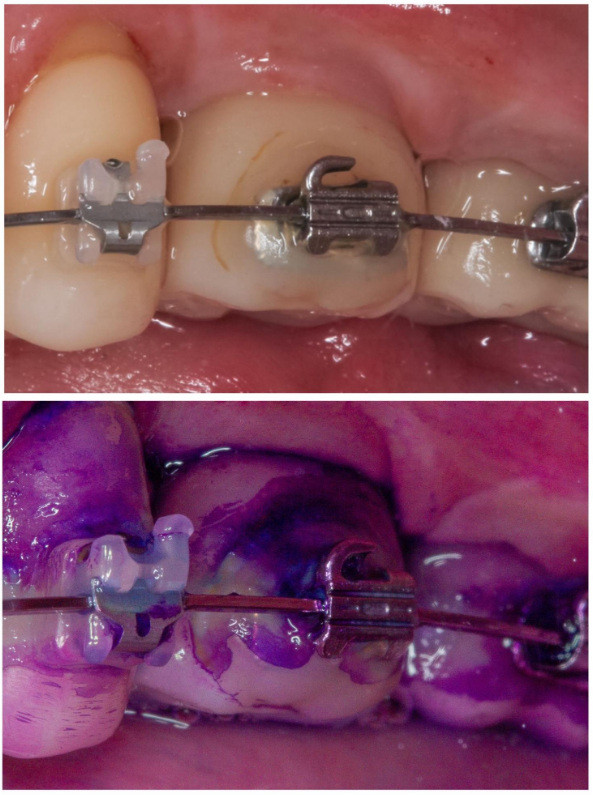

Pacjent posiada koronę na implancie, która wykorzystywana jest w leczeniu ortodontycznym. W ocenie wizualnej nic nie wskazywało na problem higieniczny. Widoczna była jedynie struktura i delikatne przebarwienie kleju ortodontycznego. Po wybarwieniu płytki nazębnej, dookoła implantu uwidoczniono bardzo gęstą warstwę płytki nazębnej dojrzałej (czyli obecnej na powierzchni minimum 2 dni), w tym kariogennej czyli kwasowej, mogącej powodować próchnicę zębów sąsiadujących.

Bez wybarwiania, które jest częścią GBT, higienistka nie wykonałaby dokładnego usunięcia warstwy bakteryjnej, nie dostrzegając jej. Brak narzędzi obecnych w GBT (piasek EMS Plus, piaskowanie poddziąsłowe) uniemożliwiałby też oczysczenie okolic szczeliny dziąsłowej, a także przy zamkach ortodontycznych i implantach. Pozostawiony biofilm to źródło procesu zapalnego, bólu i krwawienia dziąseł, próchnicy oraz dezintegracji implantów.